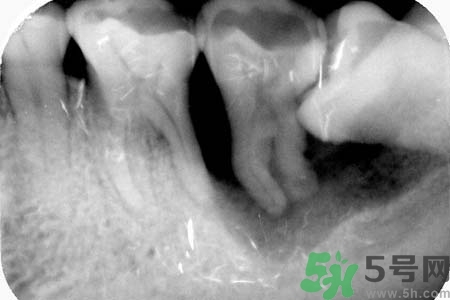

不少人長了智齒后拍片子顯示牙齒橫著在長,出血這種情況的時候該怎么辦?智齒橫著長一定要了拔嗎?關(guān)于智齒橫著長怎么辦?智齒橫著長一定要拔了嗎?智齒不疼需要拔嗎?小編為您一一解答。

如果發(fā)現(xiàn)自己的智齒橫著長了,為了不讓智齒阻生引起其他的危害,我們一定要盡快把橫著長的智齒拔除,而且不需要鑲牙,拔掉之后有助于身體健康,還可以保護(hù)附近其他牙齒。但是,我們還要重視一點,拔智齒是一種牙科門診手術(shù),要求醫(yī)生的技術(shù)水平要比較高,因為橫生的智齒,拔除的時候難度更大,首先要將黏膜切開,去骨之后才可以拔除的,這不是普通的牙醫(yī)可以把握好的。所以,小編在此提醒各位患者,務(wù)必選擇正規(guī)的牙科醫(yī)院,由專業(yè)的牙科醫(yī)生進(jìn)行拔除手術(shù)。

智齒橫著長在拔除的時候需要遵循一些原則。正常情況下,生長情況沒有出現(xiàn)異常的智齒盡量要保留下來,不要隨便進(jìn)行拔除。特別是那些生長了很多年的智齒。只有當(dāng)智齒非正常生長,出現(xiàn)一些臨床癥狀的時候,才有拔除的需要。而且,在進(jìn)行拔除手術(shù)之前,一定要先拍攝牙片,確定智齒生長異常再進(jìn)行拔除。還有,發(fā)炎的智齒也必須要拔掉。但是如果炎癥消退,而且沒有出現(xiàn)復(fù)發(fā)的話,也可以不拔。

智齒橫著長具有很大的危害,它會擠壓附近的牙齒,嚴(yán)重時會導(dǎo)致整排的牙齒看起來都不整齊。而且還會影響到患者的咀嚼功能。智齒阻生跟前牙間會容易殘留食物殘渣,積累細(xì)菌,引發(fā)齲齒或冠周炎。如果一旦出現(xiàn)冠周炎就會反復(fù)地發(fā)作。智齒橫著長還會影響牙齒的咬合,長期下來更會引發(fā)下頜疼痛、夜磨牙等。很多20多歲左右的年輕人,總是覺得牙齒疼痛,去醫(yī)院檢查都會發(fā)現(xiàn)是因為智齒橫著長。但是智齒橫著長很難察覺,通常都是是引發(fā)了疼痛,患者才會開始所察覺。